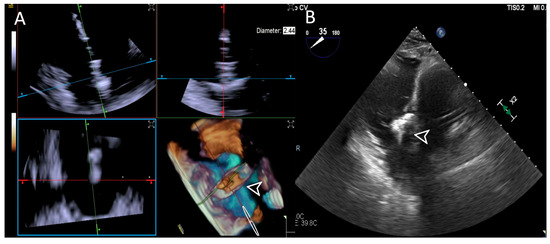

2.3. Procedural Steps

- Step number 1: assessment of tricuspid valve anatomy.

- Step number 2: identification of the target lesion.

- Step number 3: steering and valve approach.

- Step number 4: ensuring perpendicularity and correct trajectory.